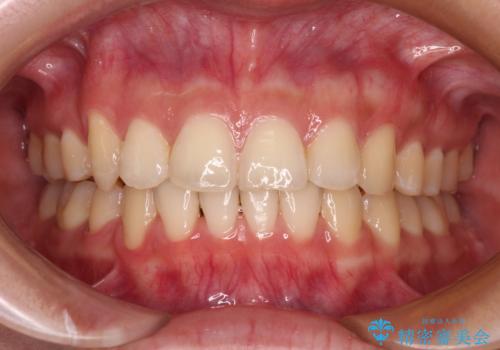

[前歯のねじれ・がたつきを治したい ]ワイヤーとマウスピースの併用矯正治療

![[前歯のねじれ・がたつきを治したい ]ワイヤーとマウスピースの併用矯正治療の症例 治療前](https://seimitsushinbi.jp/wp/wp-content/uploads/2023/11/IMG_0010-1-500x350.jpg?v=1699509973)

![[前歯のねじれ・がたつきを治したい ]ワイヤーとマウスピースの併用矯正治療の症例 治療後](https://seimitsushinbi.jp/wp/wp-content/uploads/2023/11/1c93ab7139a768f1f61b6dd35aac7324-500x350.jpg?v=1699510065)